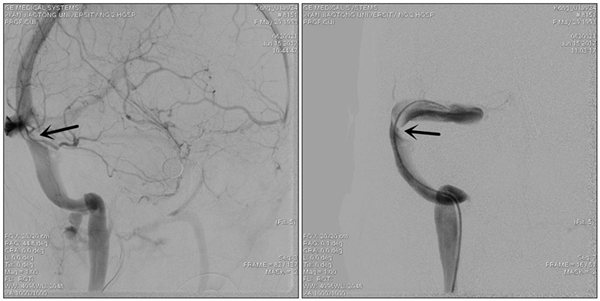

术前造影显示静脉窦狭窄

患者转入我科时头痛剧烈、烦躁不安、双眼视力仅有眼前指数,强力脱水的状态下颅内压仍大于600mmH2O。我们按压了分流阀,发现分流阀已经堵塞,家属急切的要求我们重新给她做分流手术,缓解颅内压。但崔刚、许刚二位医生仔细了解患者病史,认真研究患者的影响资料,考虑患者颅内高压、视力下降、癫痫发作这一系列症状是由于颅内静脉窦狭窄造成的,要想彻底解决这些问题的关键不是分流手术,而是恢复颅内静脉窦的正常回流。经与患者家属的充分沟通后,家属接受了我们的诊疗思路,次日为患者行全脑血管造影术,发现患者右侧横窦狭窄严重,经测量狭窄远近端压力差为310 mmH2O。根据国际指南,狭窄远近端压力差大于130 mmH2O就有实施静脉窦支架成形术的指征。为了进一步确定手术效果,崔刚、许刚二位医师先为患者实施了静脉窦狭窄球囊扩张术,球囊扩张后,患者诉头痛明显缓解、视力也开始恢复。次日腰穿显示颅内压已经降到了270mmH2O,患者及家属非常满意。